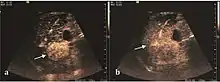

Early hepatocellular carcinoma (Early HCC)

The suggestive appearance of early HCC on 2D ultrasound examination is that of hypoechoic nodule, with distinct pattern, developed on cirrhotic liver. Hypoechoic appearance is characteristic of moderate/poorly differentiated HCC, with low or absent fatty changes. Rarely, HCC may appear isoechoic, consist of a tumor type with a higher degree of differentiation and therefore with slower development. Another common aspect is "bright loop" or "nodule-in-nodule" appearance, hypoechoic nodules in a hyperechoic tumor.

Spectral Doppler characteristics of early HCC overlap those of the dysplastic nodule, as they are represented by the presence of portal venous signal type or arterial type with normal RI (well differentiated HCC) or increased RI (moderately or poorly differentiated HCC). The CFM exploration identifies a chaotic vessels pattern.

On CEUS examination, early HCC has an iso- or hypervascular appearance during the arterial phase followed by wash out during portal venous and late phase. There are studies showing that the wash out process is directly correlated with the size and features of neoplastic circulatory bed. Thus, highly differentiated HCC illustrates the phenomenon of late or even very late "wash out" while poorly differentiated HCC has an accelerated wash out at the end of arterial phase. It is therefore mandatory to analyze all these three phases of CEUS examination for a proper characterization of liver nodules. Tumor wash out at the end of the arterial phase allows the HCC diagnosis with a predictability of 89.5%. Some authors consider that early pronounced contrast enhancement of a nodule within 1–2 cm developed on a cirrhotic liver is sufficient for HCC diagnosis. These results prove that for a correct characterization of the lesions it is necessary to extend the examination time to 5 minutes or even longer.